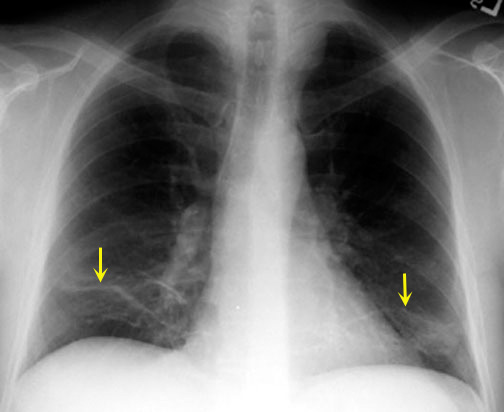

Plate like atelectasis

Plate like atelectasis (sub segmental atelectasis) is an example of focal loss of surfactant.

Note the bilateral basal plate like atelectasis.

This is an example of plate like atelectasis (yellow arrows) in a patient with pulmonary embolism.

You can also encounter plate like atelectasis whenever there is basal hypo ventilation.

• Post-op

• Obesity